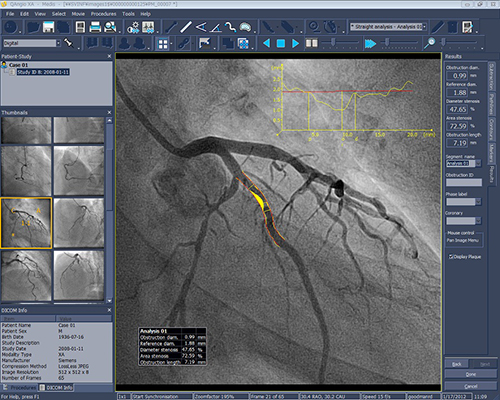

いずれも世界スタンダードといえる各種解析ソフトウェアの最新バージョンを取り揃えています。シネアンギオ解析のQAngio XAおよびCAASは定番の定量解析(QCA,QVA,LVA)を行います。心臓MR解析システムであるQMassESは一般的なシネMR解析や遅延造影解析,Perfusion解析に加え,T2強調画像からの浮腫定量化(Massk Mode),心筋サルベージの計算,T1・T2・T2*マッピング等の解析ツールを備えました。IVUS解析のQIvusでは,一般的なGrayscale解析,Tissue Characterization解析,OCT像のstent解析に加え,新しくNIRS解析も加えられました。また心エコー解析として有名なTomTec-Arenaも,各種4D解析がリニューアルされました。これら各種臨床研究ツールはGoodnetからシームレスに起動(※QMassESを除く)され,蓄積された画像データをストレスなく解析できます。

QAngio XA